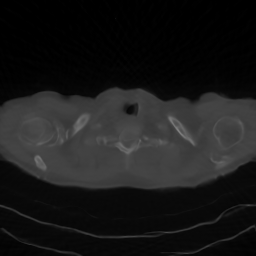

A qualitative comparison can be carried out by examining Figures 2, 3, and 4, which show the reconstructions with the zoomed region identified by the red square. The figures confirm the results reported in the tables, as the reconstructions obtained with DPS and DiffPIR contain noticeable errors. In particular, the DiffPIR reconstruction appears highly blurred and poorly defined. With respect to the images obtained using the two best-performing methods reported in the table, namely DDRM and RD-DGP, we observe that the resulting images exhibit different characteristics. In particular, the reconstructions of image C081-35 (Figure 2) appear quite similar for both methods, In contrast, for images C081-45 and C081-79, inspection of the cropped regions shown in the figures reveals that the DDRM reconstruction exhibits incorrect object shapes, whereas this effect is substantially less pronounced in the RD-DGP reconstruction. Additionally, DDRM images appear more contrasted but also noisier.

Figure 4: Visual comparison of different reconstruction methods for Sample C081-79 across three sparse-view configurations (nα=30,45,60n_{\alpha}=30,45,60). The red box indicates the zoomed region shown in the inset.